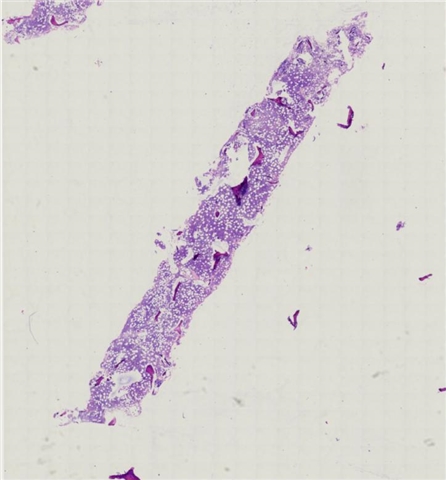

案例3 (7164)

性别:       年龄:19

患者详情: 发现颌下肿块1月,B超检查示颌下腺区域异常低回声,未见淋巴门结构,大小42*23mm,内部见较丰富血流信号,造影均匀等增强,NHL待排。行肿块穿刺活检。全身检查无肿大淋巴结。

大体所见: 巨检:条索状碎组织0.7*0.3*0.1cm。

医院: 复旦大学附属华东医院